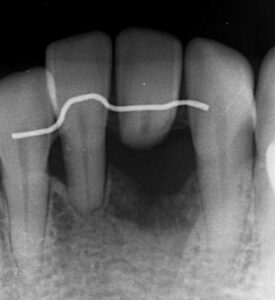

レントゲンでは抜歯した歯が浮いているように

見えます。